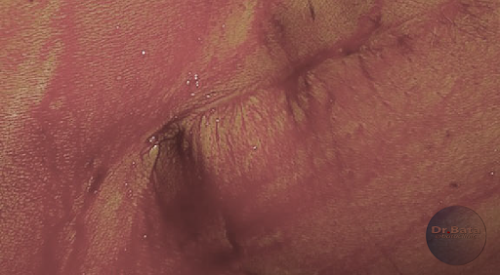

- الصورة الاولي لنمطة الارتجاع